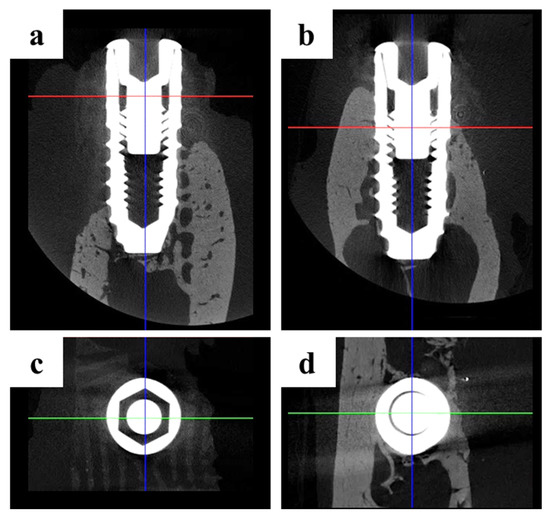

2.2.2. Findings Using Micro-Computed Tomography (Micro-CT)

4.4.4. Micro-Computed Tomography (µCT) Analysis